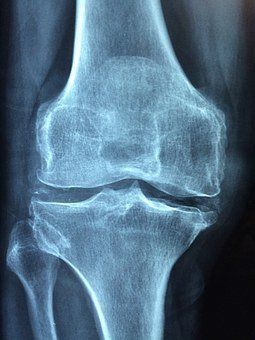

Umgangssprachlich wird häufig von "Rheuma" als Erkrankung gesprochen. Tatsächlich ist "Rheuma" aber kein eigenständiges Krankheitsbild, sondern ein Überbegriff für weit über 100 unterschiedliche rheumatische Erkrankungen. Eines haben Sie alle gemeinsam: Sie verursachen Schmerzen und Bewegungseinschränkungen an Gelenken, Muskeln, Sehnen und Knochen. Die Schmerzen sind meistens reißend bis ziehend und für die Betroffenen vor allem zermürbend. Rheumatische Erkrankungen können auch die Organe betreffen/befallen. Zu den rheumatischen Erkrankungen gehören Arthrose, Gicht und Arthritis sowie unter vielen anderen auch Fibromyalgie, Sehnen(scheiden)-Entzündungen, Schleimbeutelentzündungen und folgende Autoimmunerkrankungen: